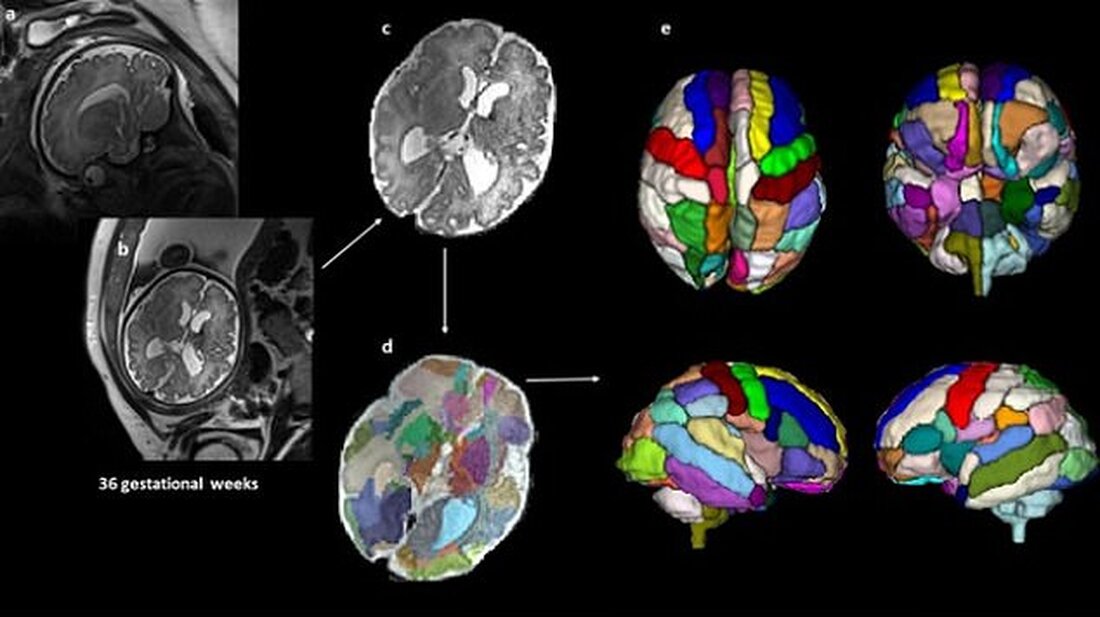

Forscher des Boston Children’s Hospital untersuchten Ultraschalluntersuchungen von 40 Babys vor ihrer Geburt. Im Bild: Ultraschalluntersuchung des Gehirns des ungeborenen Babys (a und b); ein verarbeitetes Bild des Scans, um es von anderen Körperteilen des Babys und der Mutter zu entfernen (c); der durch Farben segmentierte Gehirnscan, um die verschiedenen Teile zu zeigen (d); 3D-Versionen des Gehirns basierend auf den Scanergebnissen

Forscher unter der Leitung von Dr. Alpen Ortug untersuchten retrospektiv 39 fötale Gehirnscans, die sechs Monate nach der Empfängnis angefertigt wurden.

Das Team segmentierte dann die verschiedenen Teile des Gehirns bei jedem Scan, um sie zwischen den verschiedenen Gruppen zu vergleichen.